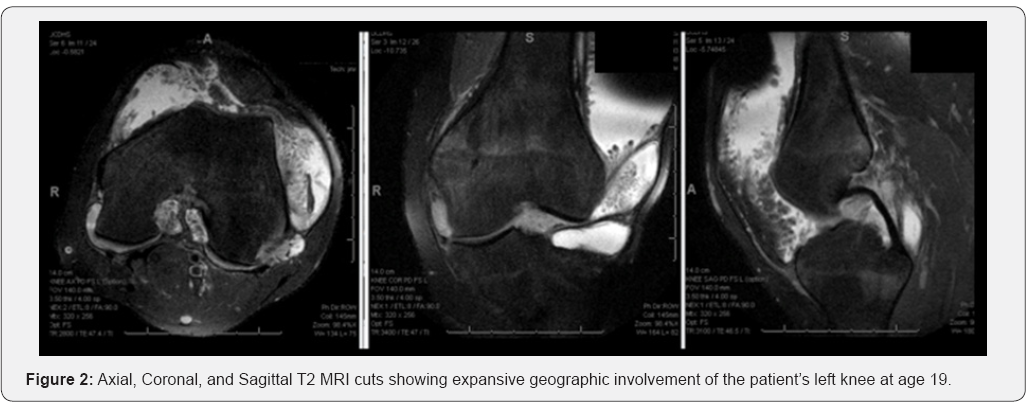

In addition to cartilaginous injury to the medial facet of the patella from his dislocations, the new MRI of his left knee revealed diffuse fatty hypertrophy of his synovium, with villous and arboreal architecture throughout the knee joint (Figure 2). An MRI was ordered for his contralateral knee given its non-painful large effusion showing similar findings of the synovium (Figure 3). Due to the severity of his recurrent effusions and difficulty performing his job duties in the automotive industry, the patient elected to have bilateral diagnostic arthroscopies with synovial biopsies and complete arthroscopic synovectomies.